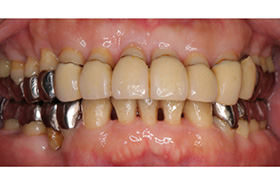

歯周病は治せます。なるべく歯を残せるような治療をしますが、再発を防ぐためには、その患者様の協力が非常に必要です。年をとっても自分の歯で食事ができるようにするためには、きちんとしたケアを実践しましょう。

Before

After